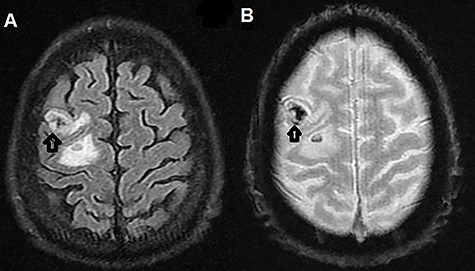

The patient was admitted to the hospital. Brain magnetic resonance imaging (MRI) revealed multiple multifocal hemorrhagic lesions with surrounding edema involving the cerebellum and both cerebral hemispheres, consistent with hemorrhagic metastatic lesions (Figs 1A, B and 2A, B).

(A) T2-weighted MRI axial image showing right parietal isointense lesion with extensive surrounding edema (black arrow); (B) T2-weighted MRI axial gradient echo sequence showing left parietal lesion compatible with hemorrhagic foci (black arrow).